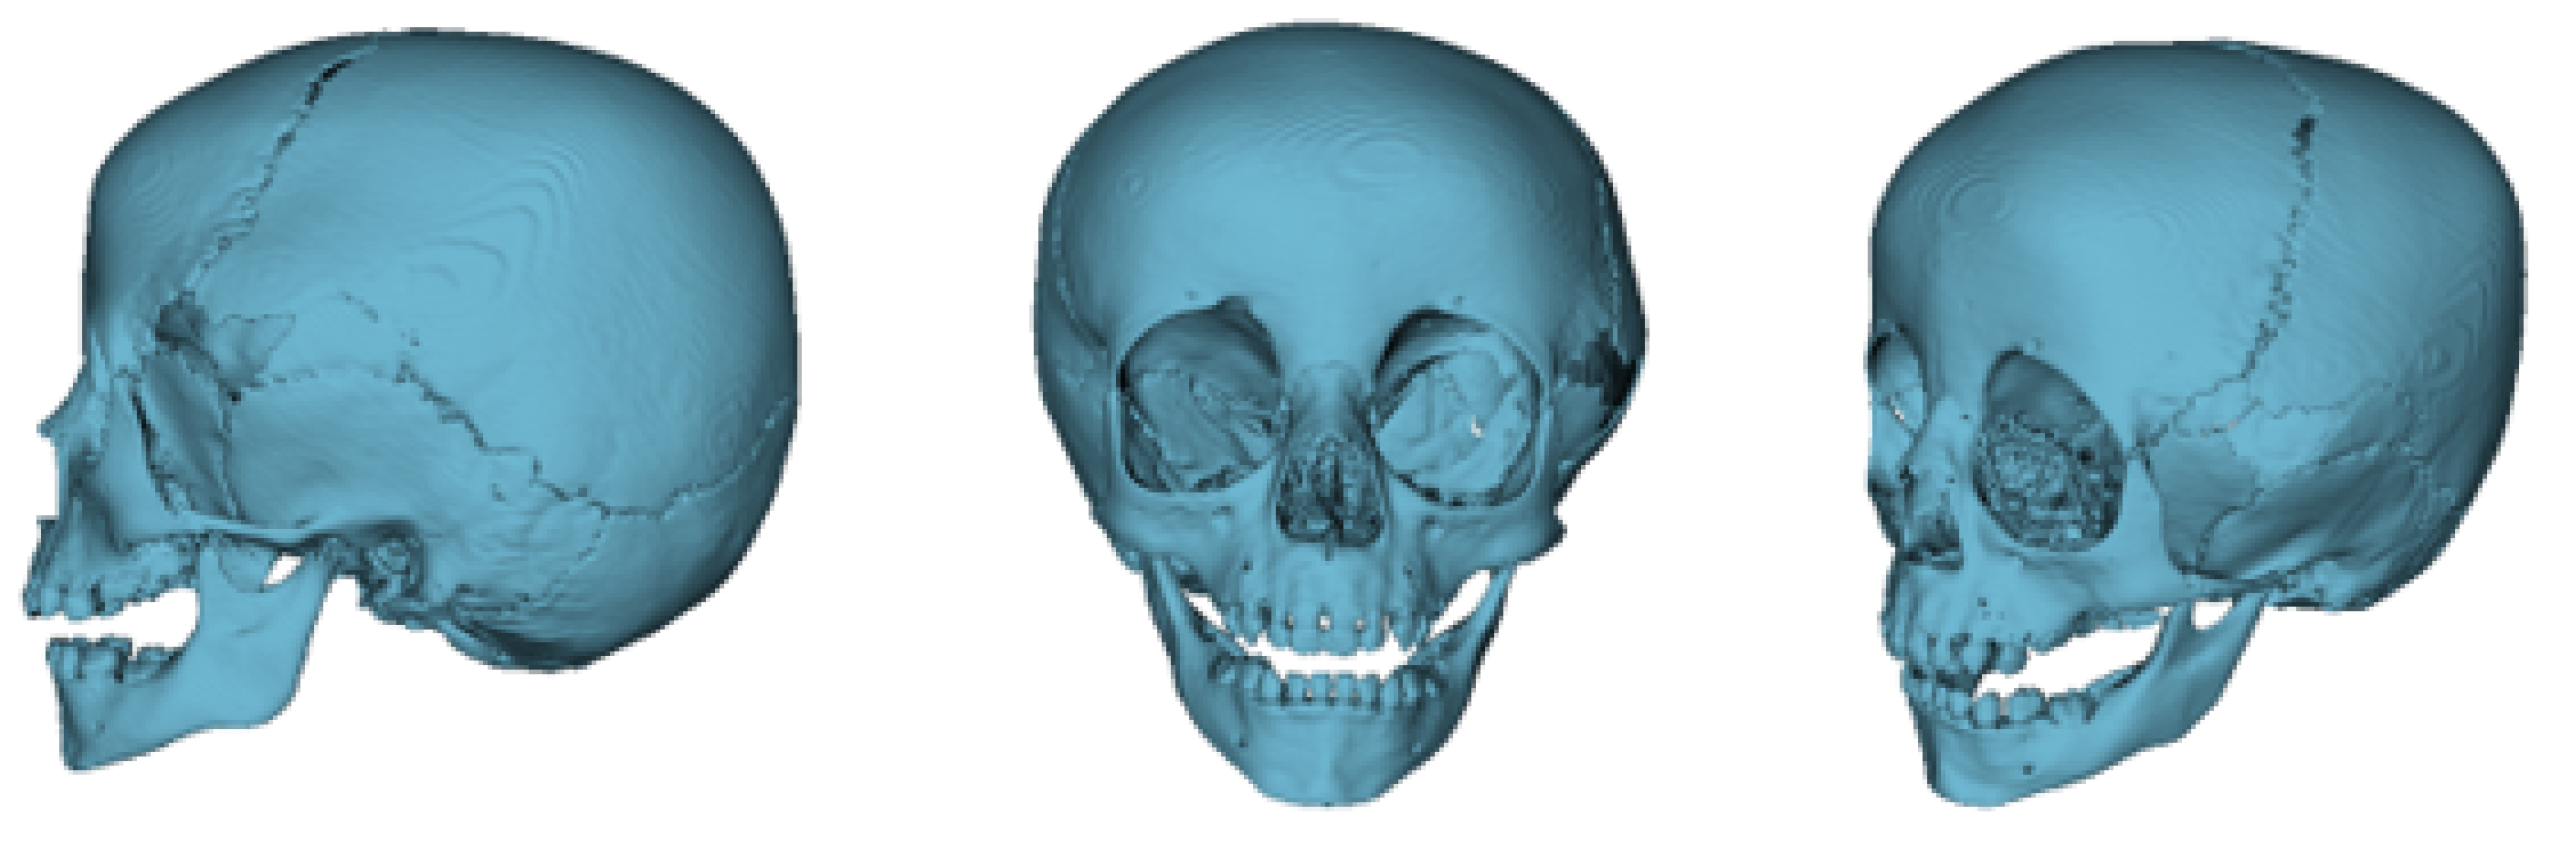

3.7.1. Diagnosis and Analysis

3.7.2. Surgical Planning

3.7.3. Design and Printing of Anatomical Models